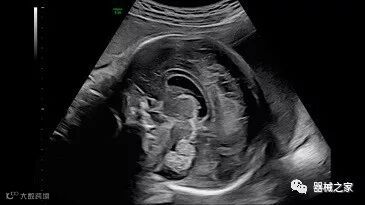

在RSNA 2018上发布的新成像被开发用于解决胎儿心脏和脑部成像问题。由于体积小且心率极快,因此难以进行详细的胎儿心脏评估。在18周时,胎儿的心脏大小与橄榄相当,每分钟跳动约150次。此外,结构本身非常复杂,婴儿不断运动,它始终是一个移动的目标。成像很重要,因为先天性心脏缺陷会影响全球每110个婴儿中的一个。

GE Healthcare用于胎儿超声的胎儿心脏和血管分析软件,在Voluson E10上提供,有助于在不到三分钟的时间内评估胎儿的心脏形状,大小和收缩性。称为辐射流的功能以三维视图显示血流。它还可以帮助显示缓慢流动的血液,例如神经血管循环。